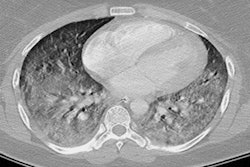

Using the telecritical care service, the researchers tracked 60 EVALI cases identified within the health network between June 27 and October 4, 2019. They defined EVALI as a clinical diagnosis based on the identification of pulmonary infiltrates on chest x-ray or CT within 90 days of electronic cigarette (e-cigarette) use and the absence of another known illness.

Overall, the group found that EVALI was associated with severe lung injury on radiological imaging and also general constitutional and gastrointestinal symptoms in nearly all the cases. Highlights from their observations of the EVALI cases included the following:

Of note, two patients originally presented with vague abdominal symptoms and were referred to the EVALI task force only after CT scans revealed bilateral ground-glass opacities in the lung bases.

The chest x-ray of a patient with vaping-associated lung injury shows lung opacities, densities, and whitish cloud-like areas common in unusual pneumonias, pulmonary edema, and lung inflammation. Image courtesy of Intermountain Healthcare.These findings are helping physicians recognize what lung injuries associated with e-cigarettes or vaping look like -- and helping them maintain a high degree of suspicion when they diagnose lung injuries in patients who've been vaping, Blagev noted.